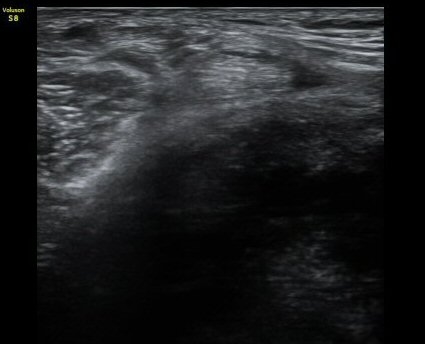

¹«¸­ ³»Ãø Á¾´Ü¸é°Ë»ç¿¡¼­ °üÀý°£°ÝÀÇ °¨¼Ò ¹× ¹Ý¿ùÆÇ¿¬°ñÀÇ ÅðÇ༺ º¯È­¿Í ¿ÜÃø À¸·Î µ¹Ãâ¿¡

ÀÇÇÑ ³»Ãø ÃøºÎÀδëÀÇ ½ÉÇÑ ¿ÜÃø µ¹Ãâ º¯ÇüÀ» º¸ÀÌ°í ³»Ãø ÃøºÎÀδë¿Í ¹Ý¿ùÆÇ¿¬°ñ »çÀÌ¿¡ ¹«¿¡ÄÚ

¼ö¾× Àú·ù°¡ °üÂûµÊ. °æ°ñ°ú ´ëÅð°ñÀÇ °ñ±ØÀÌ ¸Å¿ì ½ÉÇÑ »óÅÂÀÓ(±×¸² 1, 2).